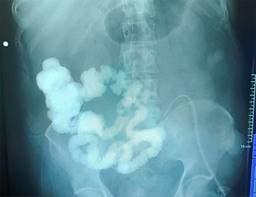

Laboratorios a su ingreso: tiempo de protrombina (TP) 17.2 segundos, índice internacional normalizado (INR, por sus siglas en inglés) 1.5, tiempo parcial de tromboplastina (TTP) 27.9 segundos; proteína C reactiva (PCR) 8.8 mg/dl, = velocidad de sedimentación globular (VSG) 50 mm/h, procalcitonina 0.63 ng/ml; leucocitos 10.66 × 109/l, neutrófilos 8.57, hemoglobina (HB) 9.8 g/dl, hematocrito (Hto) 31.1%, volumen corpuscular medio (VCM) 100.5 fl, hemoglobina corpuscular media (HCM) 31.6 pg, plaquetas 485,000/mm3; bilirrubina total (BT) 1 mg/dl, albúmina 3.3 g/dl, proteínas 5.4 g/dl, globulina 2.1 g/dl; sodio (Na) 146 meq/l, potasio (K) 4 meq/l, cloro (Cl) 111 meq/l, calcio (Ca) 7.5 meq/l, fósforo (P) 2.8 meq/l, magnesio (Mg) 1.8 meq/l, nitrógeno ureico en sangre (BUN) 12 meq/l, creatinina (Cr) 0.55 mg/dl. Tomografía sin evidencia de colecciones. Se realiza manejo y control de sepsis, así como desequilibrio hidroelectrolítico y se realiza soporte nutricional con nutrición parenteral al 100%; a los 15 días se decide reintervenir encontrando abdomen congelado; se realiza disección a través del epiplón hasta encontrar asa de intestino delgado, se coloca sonda Foley de 18 Fr con técnica de Witzel. Se realiza paso de medio de contraste, se localiza sitio de inserción de yeyunostomía en yeyuno (Figura 2), por lo cual se realiza inicio de nutrición por la misma, se inicia dieta al 100% vía oral con recolección de quimo y autotrasplante por el mismo paciente (Figura 3). A las dos semanas se realiza balance nitrogenado encontrándolo positivo, por lo que se decide su egreso y manejo ambulatorio después de 36 días de estancia hospitalaria. A los siete meses del egreso se realiza protocolo de reconexión sin complicaciones, con egresó a los siete días con recuperación total.

Figura 2: Se realiza pase de medio de contraste por sonda de yeyunostomía, a las 24 horas de la primera reintervención. Muestra paso por yeyuno, íleon y colon.